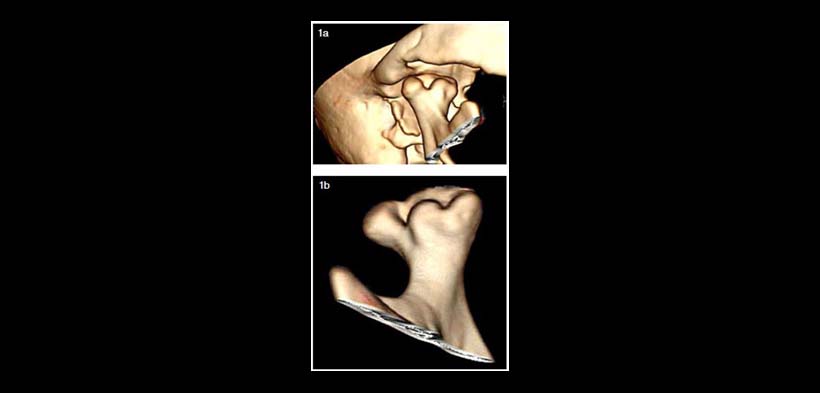

Fig. 1. Reconstrucción 3D de ATM con cóndilo trífido derecho, las depresiones o canales de eje antero posterior se aprecian delimitados a posterior por un surco de eje latero medial que separa la zona anterior. El borde condilar posterior se observa de aspecto más regular, determinando cuatro prominencias o lóbulos en el ápex condilar.